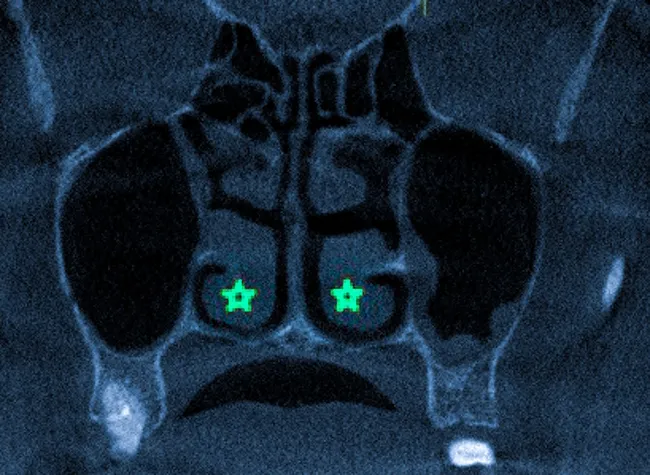

Признаки гипертрофии носовых раковин на КТ

Гипертрофия носовых раковин хорошо визуализируется при компьютерной томографии, которая помогает определить диффузную и ограниченную форму патологии. В первом случае наблюдается обширное поражение слизистой, включая затронутые участки костной структуры носовых ходов, с равномерным увеличением внутренней оболочки.

На КТ-снимке заметно равномерное утолщение нижних носовых раковин, сужение носовых ходов и отек перегородки.

Ограниченное поражение характеризуется локальным утолщением слизистой при нормальном функционировании остальных участков.

При обнаружении незначительных изменений важно учитывать предрасполагающие факторы, указывающие на высокий риск развития патологии, что видно на КТ-изображениях с деформациями и аномалиями носовой полости, хроническим воспалением слизистой и состоянием кровообращения.

На КТ-изображении пациента с хроническим гиперпластическим ринитом отмечено увеличение нижних носовых раковин (обозначенные звездочками).

На изображении звездочками указана гипертрофия нижних носовых раковин, зеленой стрелкой отмечено искривление перегородки, желтой — аномалия строения.